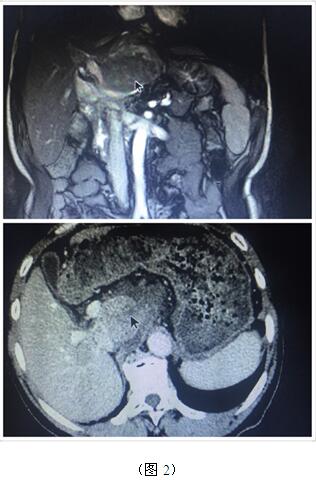

70岁高龄的曹奶奶是一个胆内胆管结石、胆总管结石、胆囊结石的高龄患者,由于结石部位多发(图1),当地医院多次住院治疗,均建议开大刀切除部分肝脏;同样患肝脏肿瘤的张爷爷,由于肿瘤位于肝脏尾叶,而且压迫腹腔大血管(图2),寻遍多家医院都只能开腹手术切除,听说衡阳市中心医院腹腔镜手术技术成熟遂慕名而来。肝胆外科周玖桥主任和李鑫副主任医师仔细分析病情后决定为俩位患者行3D腹腔镜手术。